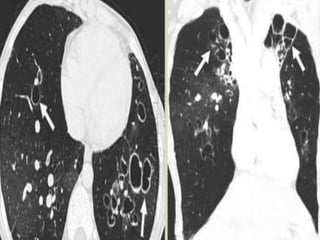

 CT is the study of choice with a sensitivity of

up to 97% and a specificity up to 99% Signet

ring appearance on CT : normally, the vessel is

larger than the corresponding bronchus

 In bronchiectasis, the bronchus is larger than

the corresponding vessel

 “Tramlines” or “honeycombing” represents

dilated, thickened bronchial walls

 Signet ring appearance on CT: normally, the

vessel is larger than the corresponding

bronchus; in bronchiectasis, the bronchus is

larger than the corresponding vessel.

 Bronchial dilation, the cardinal sign of

bronchiectasis, is characterised on HRCT by a

bronchoarterial ratio (BAR) of .1, lack of

bronchial tapering, and visibility of airways

within 1 cm of the pleural surface or abutting

the mediastinal pleural surface.

dilated, thickened bronchial walls.